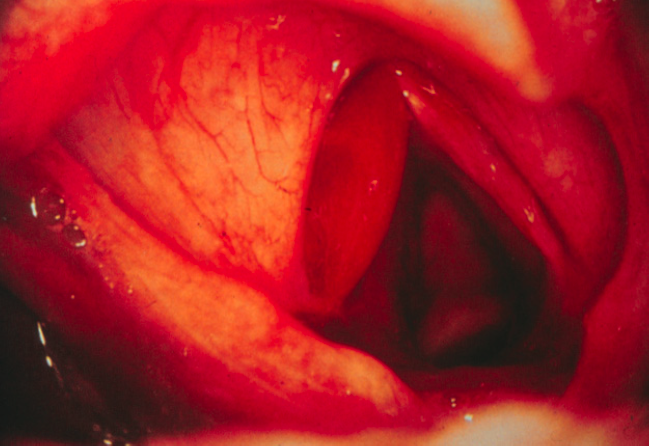

Cela peut causer un hématome, une abrasion superficielle, ou bien un granulome d’intubation. Le granulome est habituellement au tiers postérieur de la corde vocale, où la muqueuse recouvre simplement le cartilage. Si le cartilage est mis à nu, une périchondrite se développe localement, empêchant la guérison et favorisant la formation d’un granulome.

Il peut aussi y avoir une ankylose crico-aryténoïdienne, soit une immobilité de la corde vocale secondaire à la cicatrisation et à la fibrose au niveau des articulations. Cette ankylose peut être la première manifestation du traumatisme d’intubation et elle peut n’être diagnostiquée que longtemps après ce traumatisme. Les cordes vocales sont habituellement en fermeture, compromettant la voie aérienne. Il faut donc songer à cette possibilité de dx lorsque l’on voit des cordes vocales immobiles. Enfin, il peut y avoir une sténose cicatricielle.